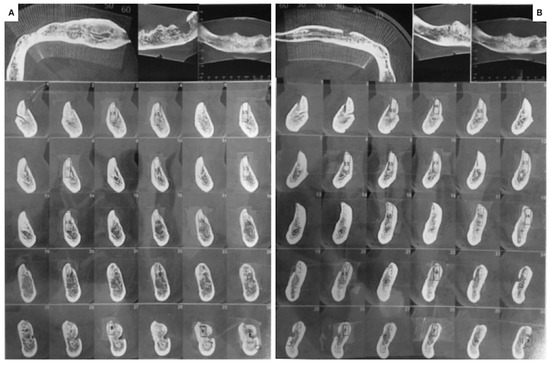

2.1.2. Histological Analysis

2.1.3. Follow Ups and Implants Insertion